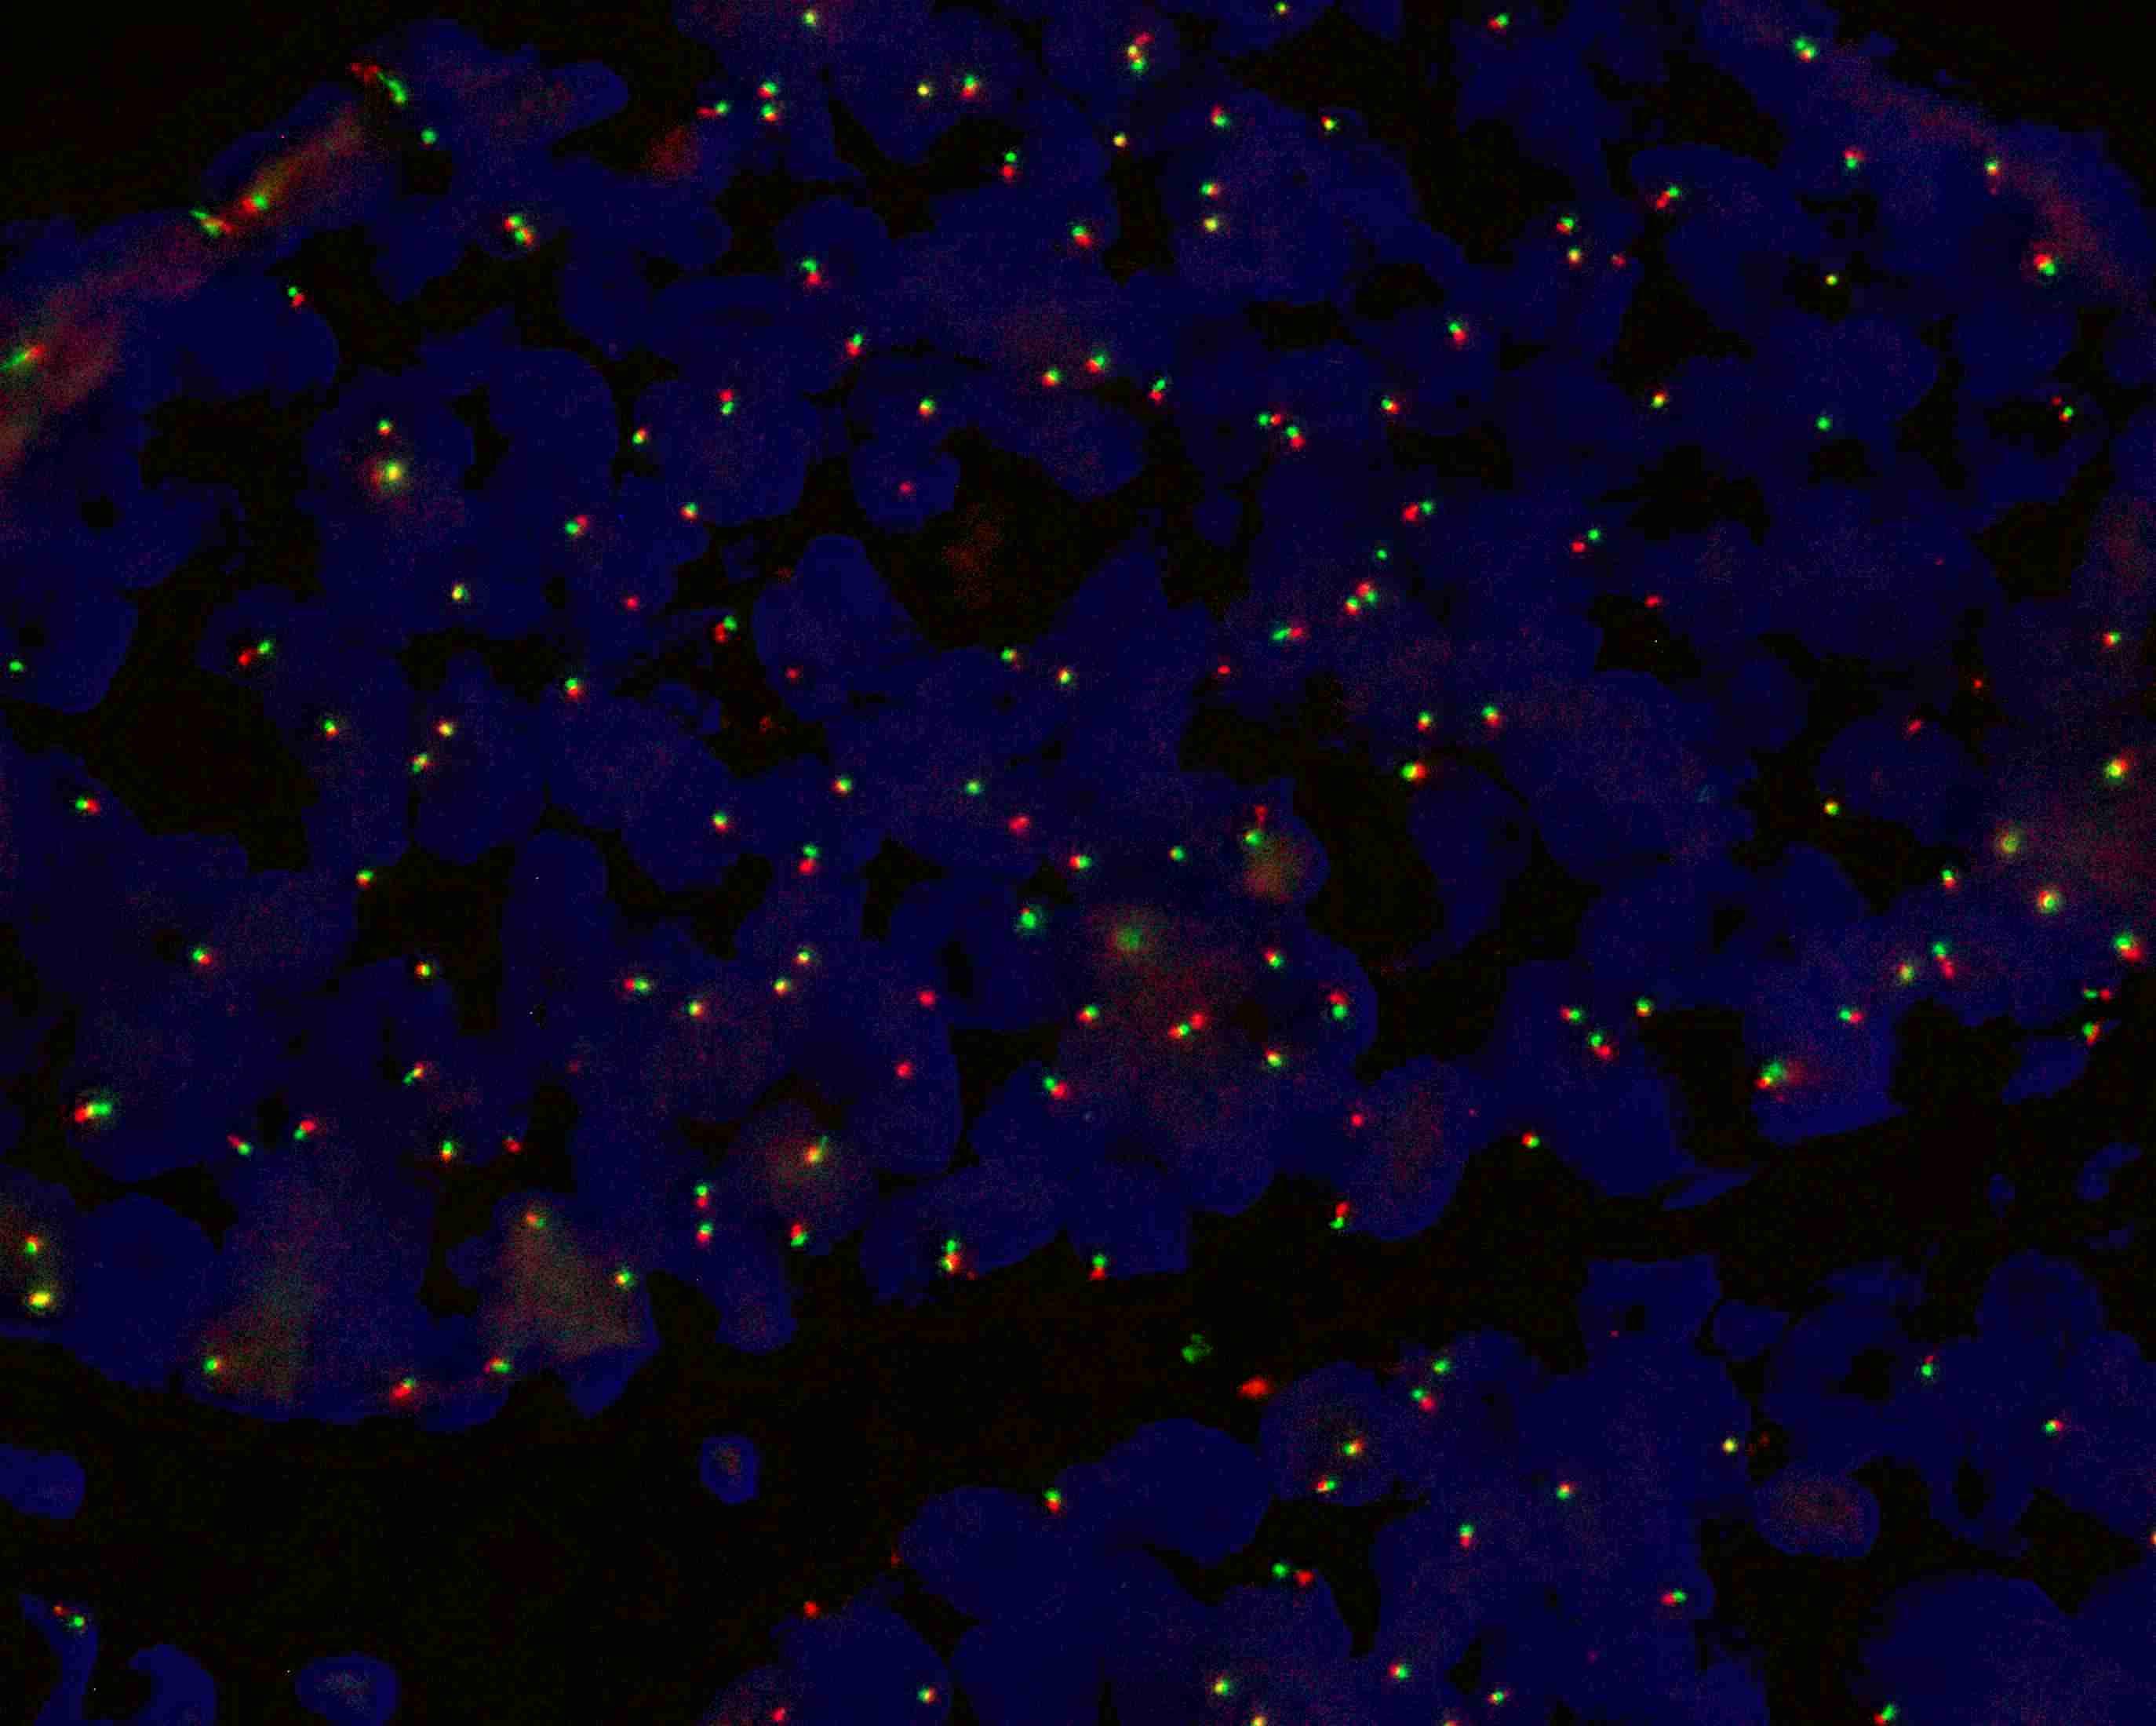

MYB gene break apart probe reagent

MYB dual color probe

MYB gene 5’ end labeled as orange, with a length of 487 kb; MYB gene 3’ end labeled as green, with a length of 777 kb.